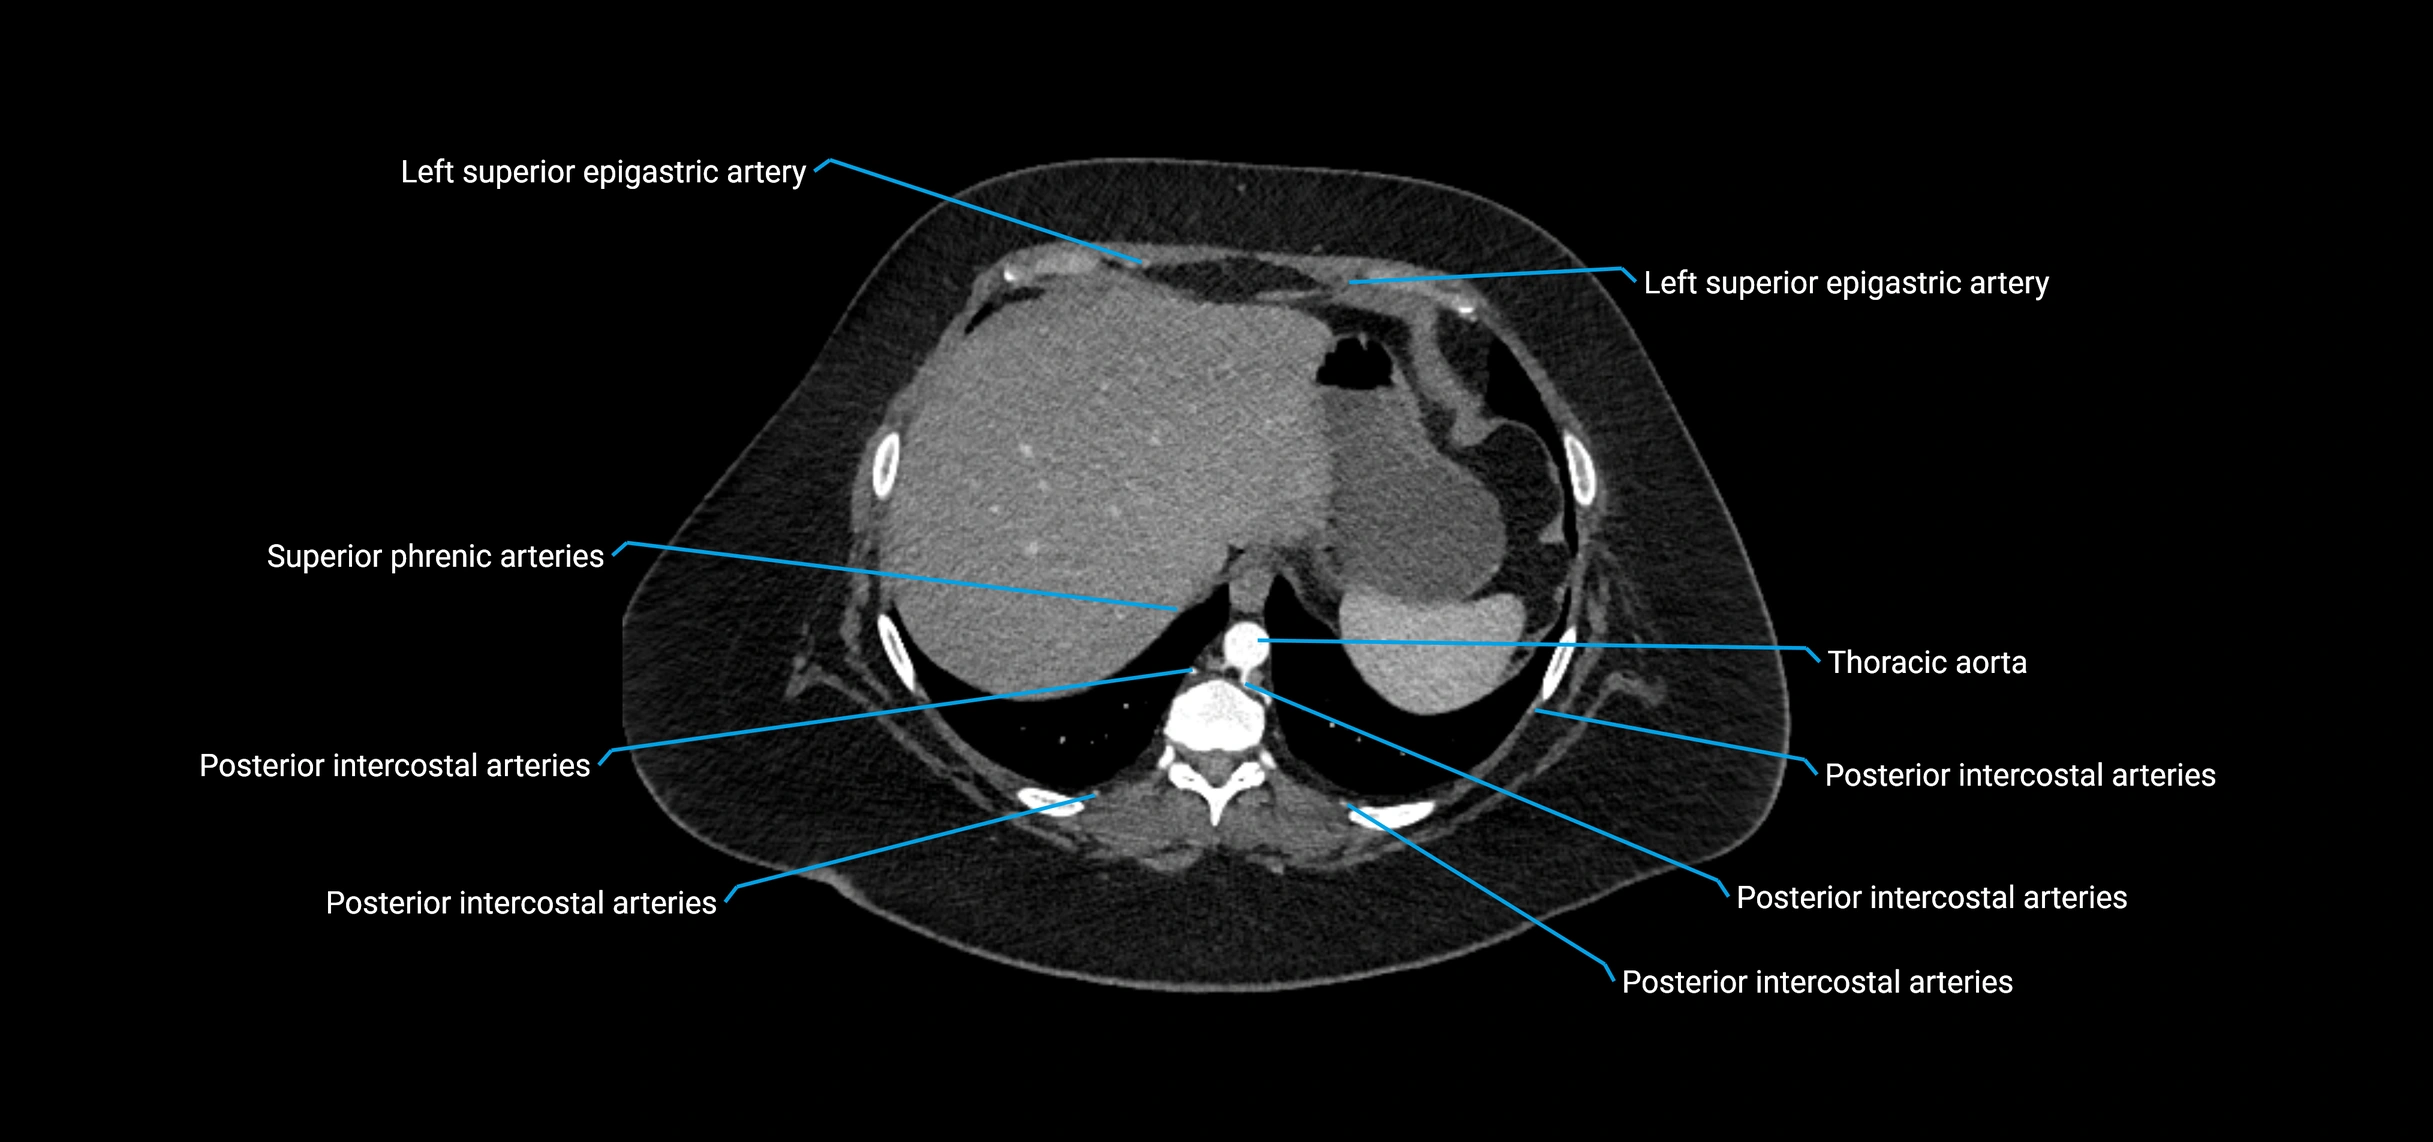

MRI images

image